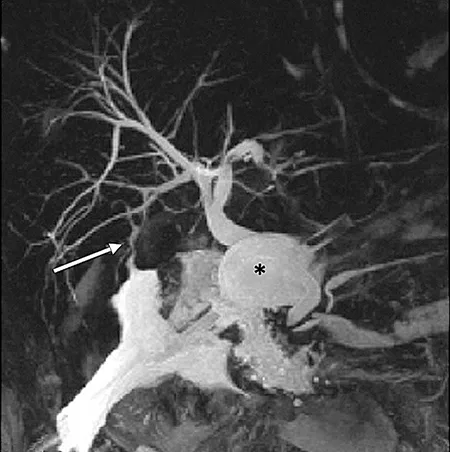

Figure 6 : Aspect en cholangio-IRM d’un kyste du cholédoque de type I (étoile) associé à une anomalie de jonction bilio-pancréatique de type II (flèche) (A). Clichés cholangiographiques obtenus par CPRE d’une anomalie de jonction bilio-pancréatique de type I (B)

La cholangio-IRM est l’examen de référence pour le diagnostic de kyste du cholédoque (figure 6A). La cholangio-IRM permet de confirmer le diagnostic par la visualisation d’une communication entre la dilatation kystique et les voies biliaires et par l’élimination des principaux diagnostics différentiels, notamment des kystes extra-biliaires non communiquants. L’IRM hépatique permet également l’évaluation du retentissement du kyste sur le parenchyme hépatique (dysmorphie hépatique, abcès) et le dépistage des complications (cancers, hypertension portale). La visualisation d’une AJBP en IRM est essentielle pour distinguer un kyste du cholédoque d’un gros cholédoque du sujet âgé ou secondaire à une cholécystectomie (cf. supra). En cas de doute sur l’existence d’une AJBP qui peut être de visualisation difficile sur la cholangio-IRM, l’écho-endoscopie bilio-pancréatique permet généralement de confirmer le diagnostic. Compte tenu du risque important d’angiocholite, la réalisation d’une CPRE diagnostique (figure 6B) doit être réservée aux suspicions de cholangiocarcinome afin de réaliser des prélèvements histologiques.